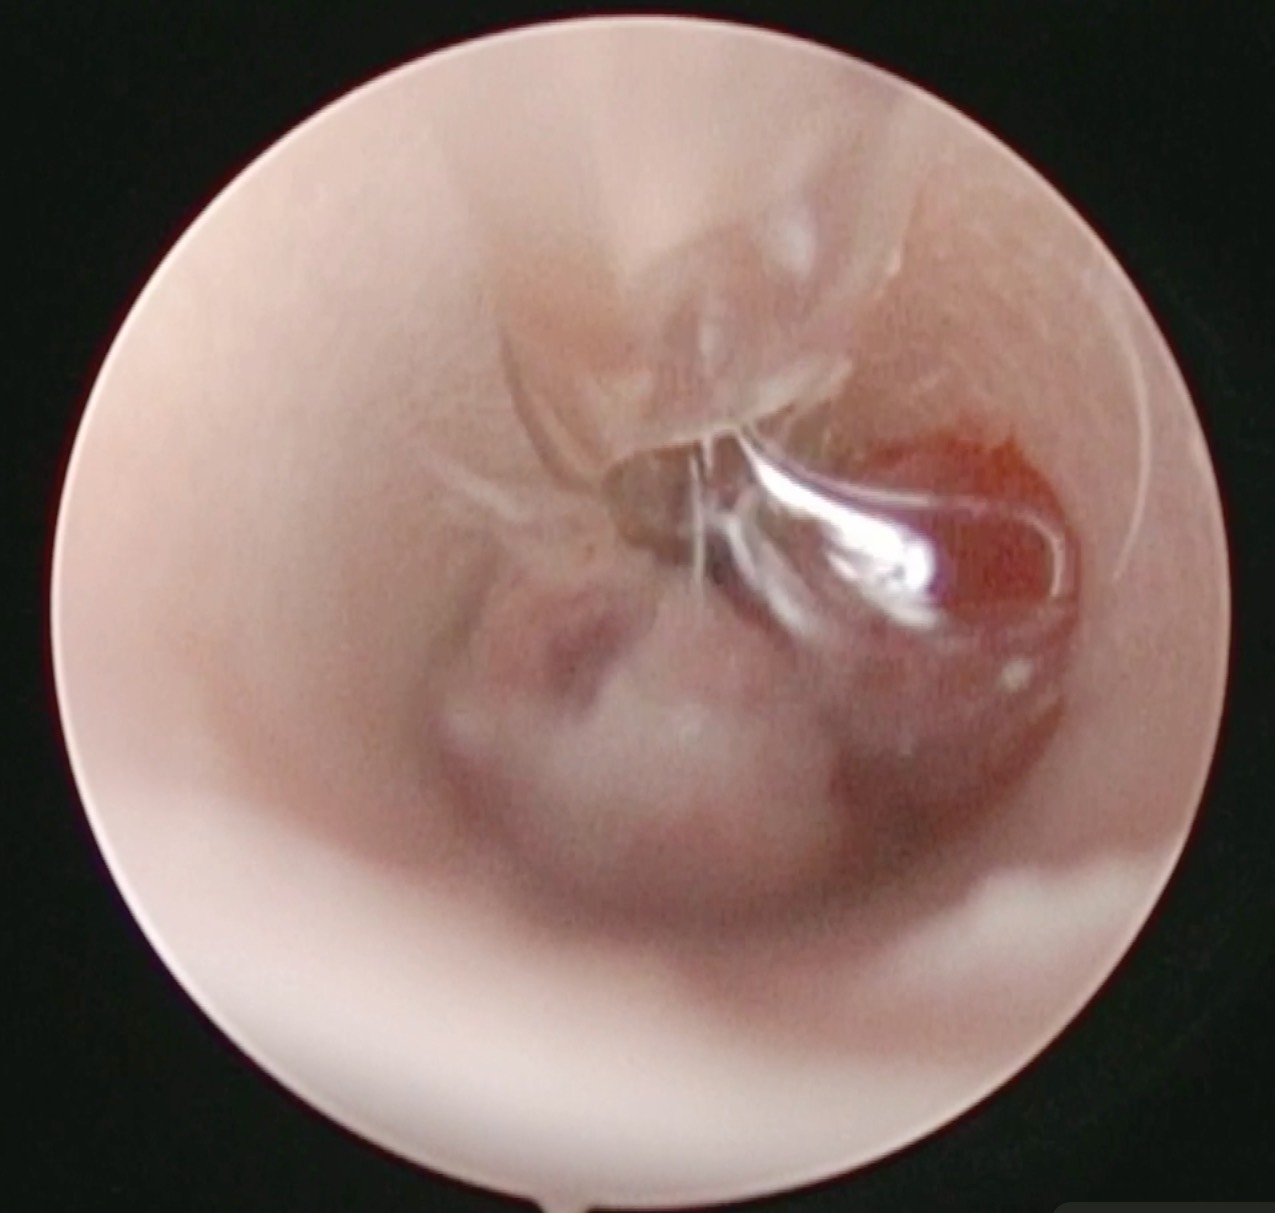

切除できそうなものなのかオトスコープで判断することができます。

腫瘤を摘出した様子